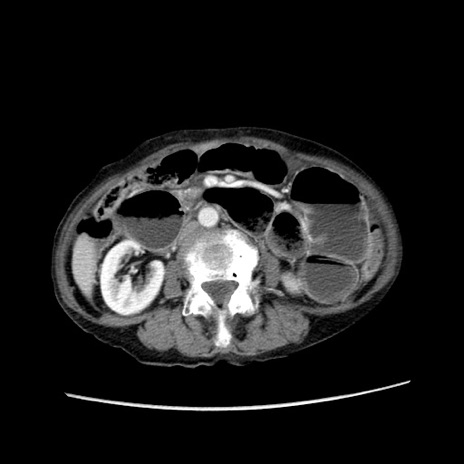

症例25(横断像)

【症例】80歳代女性

【主訴】胸のつかえ感

【現病歴】約9時間前に食後から胸のつかえた感じあり、嘔吐あり、来院。

【既往歴】胃癌(全摘)、胆摘、虫垂炎

【身体所見】心窩部に圧痛あり、反跳痛なし。

【データ】WBC 5700、CRP 0.05